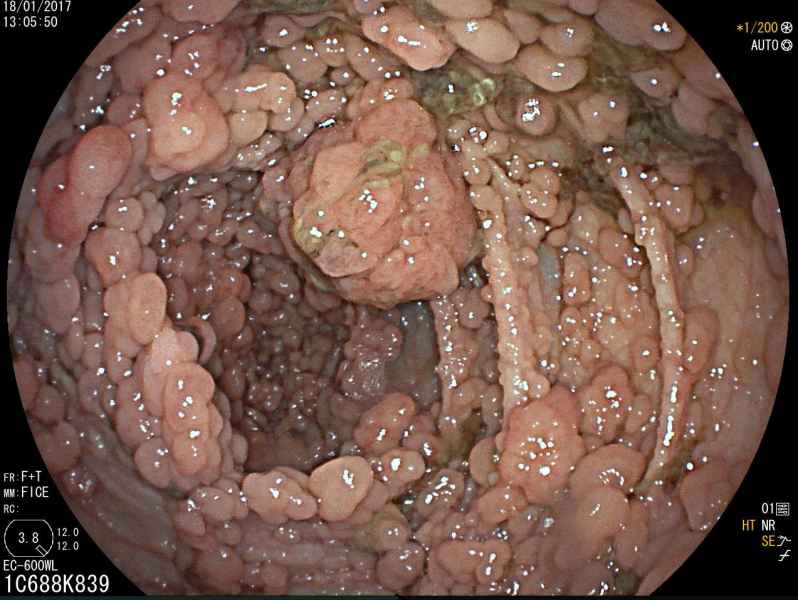

A Sea of polyps

Fotografia